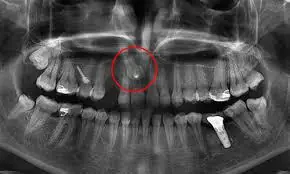

Dientes Retenidos:

Los dientes retenidos son piezas dentales que por algún motivo no han podido emerger en el tiempo adecuado, o bien dientes que se formaron de más y están dentro del hueso en lugar de emerger hacia la boca. En ocasiones los dientes retenidos pueden ser reposicionados en boca mediante la tracción con tratamiento ortodontico logrando así que el diente cumpla su función, otras ocasiones los dientes retenidos tienen que ser extraídos por ser causa de alguna patología, como quistes dentigeros o provocan la reabsorción de las raíces de los dientes contiguos.